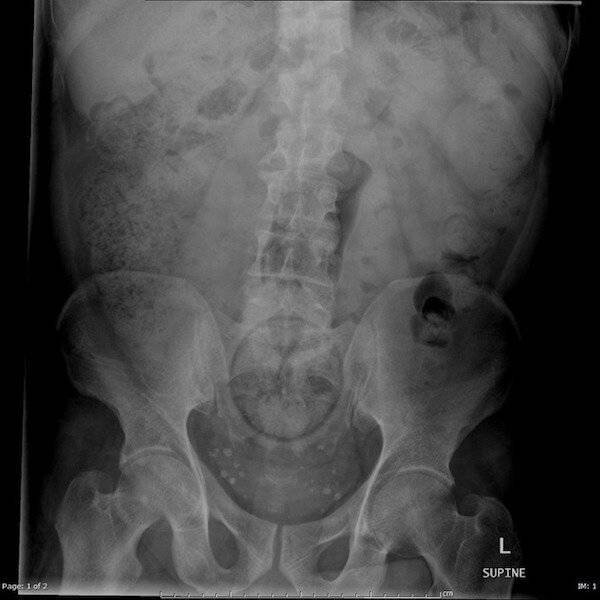

2. Бутылка "Пепси"